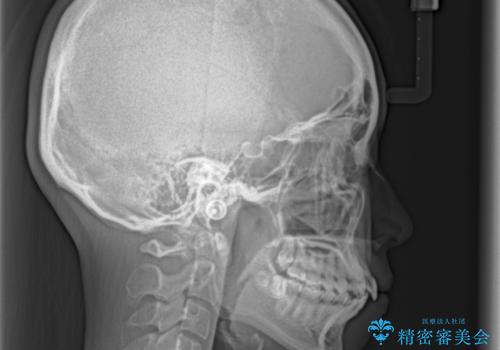

- 前歯のデコボコとクロスバイトを気にして来院された患者様です。

上顎側切歯(上の真ん中から2番目の歯)が舌側転位している場合、インビザラインでは仕上げきれないことが多く、更には無理して動かそうとすると歯髄壊死を起こすリスクが高いと言われています。

今回は、ワイヤー装置を併用することなく、インビザライン単体で矯正治療を行うこととしました。